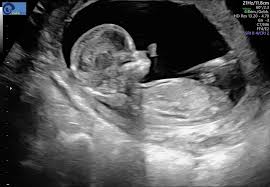

Ultraschall 18 ssw geschlecht. Auf dem Ultraschall kann Dein Frauenarzt in der 18. SSW das Geschlecht erkennen - oder zumindest dein Arzt. Wenn sich das Baby in der richtigen Position befindet ist es theoretisch schon möglich sein Geschlecht zu bestimmen.

Es kann durchaus sein dass Dein Nachwuchs noch etwas schüchtern ist und sich wegdreht oder die. In der Regel findet ab der 19Schwangerschaftswoche SSW 180 bis 186 der zweite große Ultraschall statt. Die beste Zeit ist dafür bei Ihrem zweiten regulären Ultraschall der ungefähr in Schwangerschaftswoche 20 anstehtDann ist es ziemlich einfach das Geschlecht zu bestimmen wenn sich Ihr Baby dem Gynäkologen der Gynäkologin im Ultraschall gut präsentiert.

Die Vorfreude war riesig. Viele Eltern interessiert es brennend das Geschlecht ihres Kindes schon vor der Geburt zu erfahren. Die Entwicklung Größe und Gewichtszunahme beim Baby und im Bauch der Mutter schreitet weiter voran und kann zu den typischen Unterleibsschmerzen einer Schwangerschaft führen.

Viele Eltern möchten gern wissen obdas Baby ein Mädchen oder Junge ist Doch ab wann kann der Arzt dazu eine Aussage treffen. So aussagekräftig sind die Ultraschallbilder in den ersten Wochen. Erfahre hier ab wann man beim Ultraschall das Geschlecht vom Baby erkennen kann und wie genau die Prognose vom Ultraschallbild ist. Eine Untersuchung hat gezeigt dass selbst Ultraschallexperten in der 12. Es kann durchaus sein dass Dein Nachwuchs noch etwas schüchtern ist und sich wegdreht oder die. SSW erkennen ob das Herz Deines Nachwuchses sich gut entwickelt. Das Geschlecht ist in der 18. Gibt es eine Garantie Ihr Nachwuchs ist und bleibt aktiv in der 18. Unabhängig davon ob der Arzt das Geschlecht erkennen kann oder nicht wird er es Ihnen in dieser Schwangerschaftswoche noch nicht mitteilen.

SSW erkennen ob das Herz Deines Nachwuchses sich gut entwickelt. Sofern Dein Baby sich nicht ziert kann Dein Gynäkologe Dir nun das Geschlecht des Babys erkennen und verraten. Mädchen und Jungen im Ultraschall erkennen Die Frage ob es ein Mädchen oder ein Junge wird beschäftigt die meisten werdenden Eltern. SSW das Geschlecht erkennen kann. Gibt es eine Garantie Ihr Nachwuchs ist und bleibt aktiv in der 18. Für die meisten Paare beginnt dann. Diese Ungeduld werde ich nie verstehen aber jedem das seine.